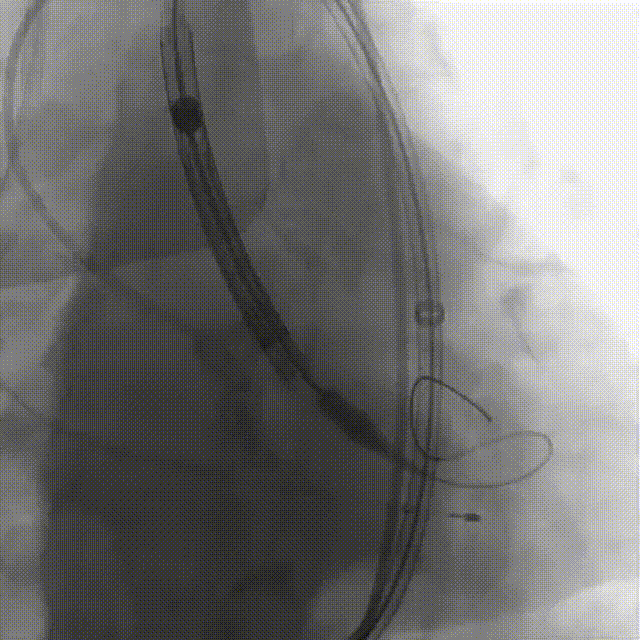

刘煜昊教授 阜外华中心血管病医院(点击查看专家详细简历) 首瓣选耐久,干瓣护航全生命周期管理 2025年ESC专家共识里指出:“推荐第一个瓣膜要选经证实具有长期耐用性的外科瓣膜与经导管瓣膜,以降低再次介入治疗的可能性 ,对于瓣环较小、根据预测有效瓣口面积(EOA)评估存在严重 PPM 风险的患者,可采用主动脉根部扩大术联合 SAVR,或植入环上瓣,对于小瓣环患者自展瓣拥有比较好的血流动力学优势”。 每一次术前评估,都是我们与患者携手面对未知的起点。我们始终以患者全生命周期获益为核心,在瓣膜选择与术式规划中,不只着眼于当下解剖适配,综合评估解剖条件、预期寿命与生活质量。从年轻患者到高龄人群,瓣膜耐久性与血流动力学稳定性始终是决策核心! 陈同峰教授 阜外华中心血管病医院(点击查看专家详细简历) 医学的进步正不断拓宽生命的边界,每一次术前评估都是对生命尊严的深度凝视,技术与人文的交融,让风险不再仅是数字的堆叠,而是成为医者与患者共同面对未知的勇气见证。术中瓣膜释放结束,到了导管测压的时候,我惊喜:瓣膜不错啊,压差为0,这不仅仅得益于瓣膜形态的设计,更是环上瓣及瓣叶材质优质的体现,感受到了 Prostyle A瓣膜在血流动力学上的卓越表现,其采用的抗钙化处理技术有效延长了瓣膜的耐久性,为患者长期生存提供了更可靠的保障。 患者病史 主诉:心慌半月; 门急诊诊断:心悸,冠状动脉粥样硬化性心脏病,心脏瓣膜病,主动脉瓣狭窄,高血压,甲状腺术后; 现病史:半月前无明显诱因出现心慌,呈间断性,伴心悸、出汗,伴头晕,无咳嗽、咳痰,无恶心、呕吐,无双下肢水肿,无放射痛及意识障碍,休息约几分钟后可自行缓解,症状反复发作,遂来我院就诊。 术前超声提示:室间隔增厚;主动脉瓣退行性变并重度狭窄;升主动脉明显增宽;室间隔增厚。 术前CT 三叶瓣,轻度钙化集中在无窦和左窦瓣叶边缘,主动脉根部直径19.3mm,LVOT直径17.7mm,LVOT向下收窄; 窦部正常,VTC空间足够,冠脉风险低; 左室腔小,收缩末径20-25mm,“自杀左室”,循环崩溃风险高;主动脉瓣环水平夹角71.1°,横位心,过弓和跨瓣存在一定困难,备snare。 外周双侧入路内径可,双侧入路能够支持20F大鞘通过,右股低分叉。 手术策略 推荐右侧股动脉为主入路,左侧为辅助入路,右股分叉上方1cm穿刺;推荐选择AV23瓣膜,18mm球囊预扩,左右重叠位:LAO 7° CAU 35°;左冠切线位:LAO 27° CRA 16°;右窦居中位:LAO 18° CAU 9°;备Snare,建议ECMO/CPB湿备,术前术中积极补液,警惕循环崩溃风险。 手术过程 在右股动脉穿刺建立通路后,顺利送入大鞘,经食道超声及血管造影确认路径稳定。18mm球囊预扩过程中,患者血压一度下降,迅速完成扩张并立即植入AV23 ProStyle A®瓣膜。瓣膜精准释放于目标位置,超声显示无明显反流及瓣周漏,血流动力学即刻改善。 主动脉根部造影 18mm球囊预扩少量反流 输送系统柔顺跨瓣 精准定位 平稳释放 80%工作位观索位置合适 释放后导管测压,压差由术前53mmHg降为0mmHg 最终造影瓣膜位置形态良好,冠脉灌注良好,无明显瓣周漏 ProStyle A®预装干瓣——助力临床最优化解决方案: 轻松过弓,精准可控:该病例为横位心,在未使用snare的情况下,过弓和跨瓣柔顺,较细的尺寸+柔顺的输送系统通过性能得到了很好的验证; 平衡的收腰设计:该病例瓣环较小且左室腔小,AV23瓣膜的平衡收腰设计既确保了锚定安全性,又保证了EOA,有效降低了循环崩溃风险,而术后0mmHg的压差的表现更加证明了优秀的血流动力学,提高了瓣膜的耐久性; 预装干瓣 便捷顺安:金仕生物专利抗钙化技术运用纳米技术去除组织内的细胞碎片和磷脂,封闭游离醛基,从根本上阻断了瓣膜钙化的多项因素,显著提升了瓣膜的耐久性;同时,相比较传统戊二醛保存方式,干式存储最大限度的保留心包的亲水亲油平衡,还原组织天然曲柔性,进一步保障了瓣叶开合,保证长期耐久性。 专家简介 王小虎 阜外华中心血管病医院(点击查看专家详细简历) 陈冲 阜外华中心血管病医院(点击查看专家详细简历) 赵一品 阜外华中心血管病医院(点击查看专家详细简历)